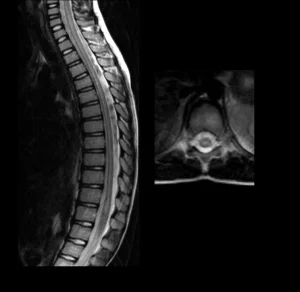

MRI (Manyetik Rezonans Görüntüleme)

MRI, miyelit tanısında önemli bir görüntüleme tekniğidir. Omurilikteki iltihaplanma ve hasar, MRI taramalarıyla net bir şekilde görülebilir. MRI, miyelit teşhisi koymada ve iltihabın yayılma derecesini belirlemede kullanılır.